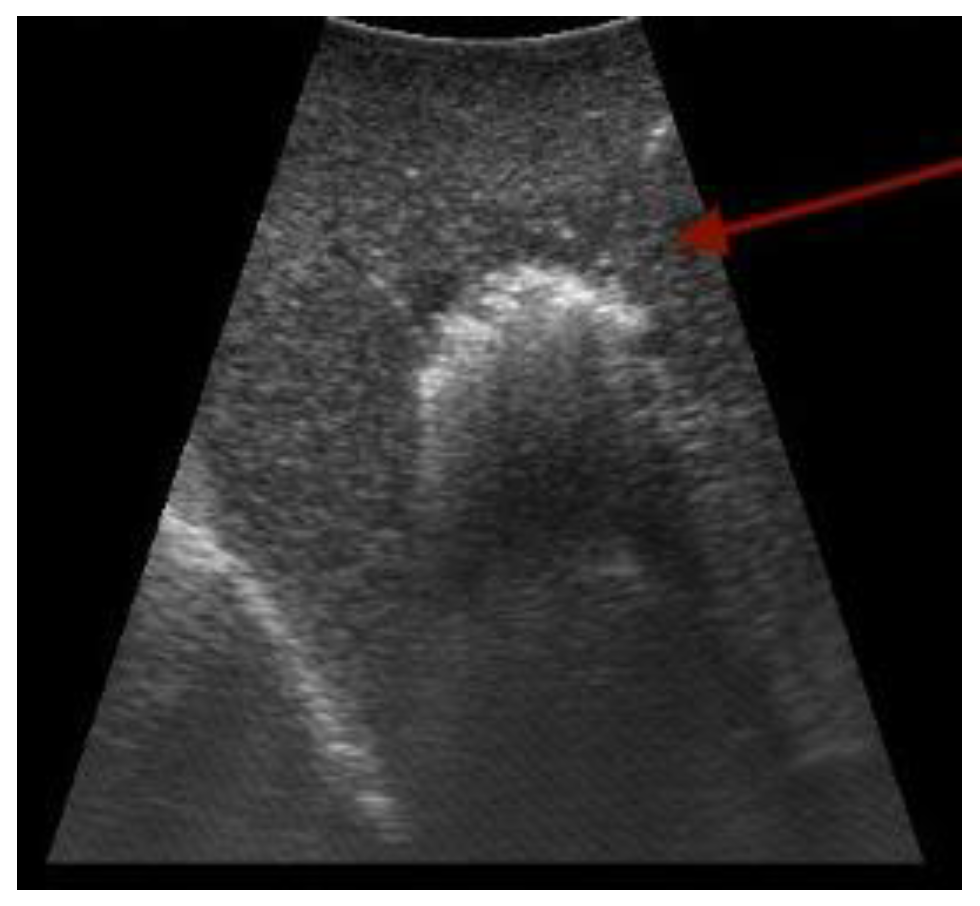

- Bartos, A.; Iancu, I.; Ciobanu, L.; Badea, R.; Sparchez, Z.; Bartos, D.M. Intraoperative ultrasound in liver and pancreatic surgery. Med. Ultrason. 2021, 23, 319–328. [Google Scholar] [CrossRef] [PubMed]

- Hoch, G.; Croise-Laurent, V.; Germain, A.; Brunaud, L.; Bresler, L.; Ayav, A. Is intraoperative ultrasound still useful for the detection of colorectal cancer liver metastases? HPB 2015, 17, 514–519. [Google Scholar] [CrossRef] [PubMed]

- Torzilli, G.; Montorsi, M.; Donadon, M.; Palmisano, A.; Del Fabbro, D.; Gambetti, A.; Olivari, N.; Makuuchi, M. “Radical but conservative” is the main goal for ultrasonography-guided liver resection: Prospective validation of this approach. J. Am. Coll. Surg. 2005, 201, 517–528. [Google Scholar] [CrossRef]

- Sahani, D.V.; Kalva, S.P.; Tanabe, K.K.; Hayat, S.M.; O’Neill, M.J.; Halpern, E.F.; Saini, S.; Mueller, P.R. Intraoperative US in patients undergoing surgery for liver neoplasms: Comparison with MR imaging. Radiology 2004, 232, 810–814. [Google Scholar] [CrossRef]

- Torzilli, G.; Del Fabbro, D.; Palmisano, A.; Donadon, M.; Bianchi, P.; Roncalli, M.; Balzarini, L.; Montorsi, M. Contrast-enhanced intraoperative ultrasonography during hepatectomies for colorectal cancer liver metastases. J. Gastrointest. Surg. 2005, 9, 1148–1153; discussion 1153–1144. [Google Scholar] [CrossRef]

- Shah, A.J.; Callaway, M.; Thomas, M.G.; Finch-Jones, M.D. Contrast-enhanced intraoperative ultrasound improves detection of liver metastases during surgery for primary colorectal cancer. HPB 2010, 12, 181–187. [Google Scholar] [CrossRef]